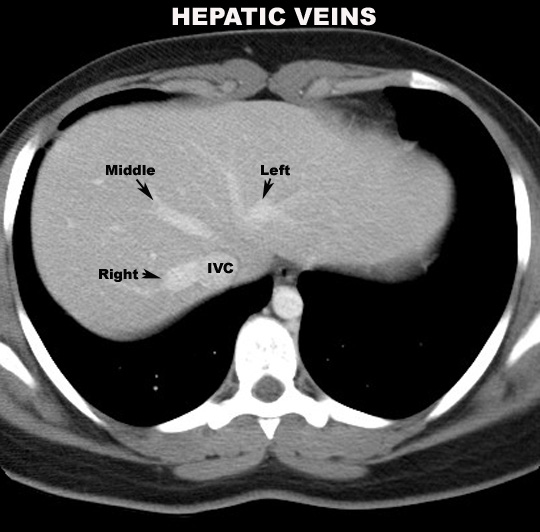

Right, middle and left hepatic veins Click the image for labeling.